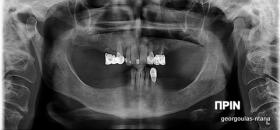

ΟΛΙΚΗ ΑΠΟΚΑΤΑΣΤΑΣΗ ΑΝΩ Κ ΚΑΤΩ ΓΝΑΘΟΥ ΜΕ ΕΜΦΥΤΕΥΜΑΤΑ, ΑΜΕΣΗ ΦΟΡΤΙΣΗ Κ ΑΝΟΙΚΤΗ ΑΝΥΨΩΣΗ ΙΓΜΟΡΕΙΟΥ

Η ασθενής αυτή είχε παλιές ακίνητες αποκαταστάσεις (γέφυρες) στην άνω γνάθο  κ μια κινητή προσθετική αποκατάσταση (μερική οδοντοστοιχία-"μασελάκι") στην κάτω γνάθο. Ήταν δυσαρεστημένη τόσο με την εμφάνιση όσο και με τη λειτουργία των δοντιών της καθώς παραπονιόταν ότι  είχαν εντονη κινητικότητα ενώ και οι προσθετικές τους εργασιές δεν ήταν σταθερές. Η πρόγνωση των δοντιών κρίθηκε φτωχή με αποτέλεσμα να μην είναι δυνατή η συμμετοχή τους σε μια νεα προσθετική αποκατάσταση με μακροχρόνια διάρκεια. Η ασθενής επιθυμούσε οι νέες αποκαταστάσεις να είναι σταθερές και ακίνητες.  Για το λόγο αυτό αποφασίστηκε η ολική αποκατάσταση της άνω κ κάτω γνάθου με ακίνητες επιεμφυτευματικές εργασίες. Στην αριστερή πλευρά της άνω γνάθου, λόγω μη επαρκούς οστού για την τοποθέτηση εμφυτευμάτων προηγήθηκε επέμβαση ανοιχτής  ανύψωσης ιγμορείου άντρου με τη χρήση πιεζοχειρουργικού μηχανήματος ώστε να δημιουργηθεί το κατάλληλο οστικό υπόστρωμα. Ακολούθησε σε επόμενο χειρουργείο η εξαγωγή των υπάρχοντων δοντιών κ η άμεση τοποθέτηση εμφυτεύματων (άμεση εμφύτευση) κ δύο μέρες μετά η τοποθέτηση προσωρινής εργασίας επί των εμφυτευμάτων (άμεση φόρτιση) με αποτέλεσμα η ασθενής να μη μείνει καθόλου χωρίς δόντια κ να είναι καλυμένη αισθητικά όσο καιρό διήρκησε η εργασία